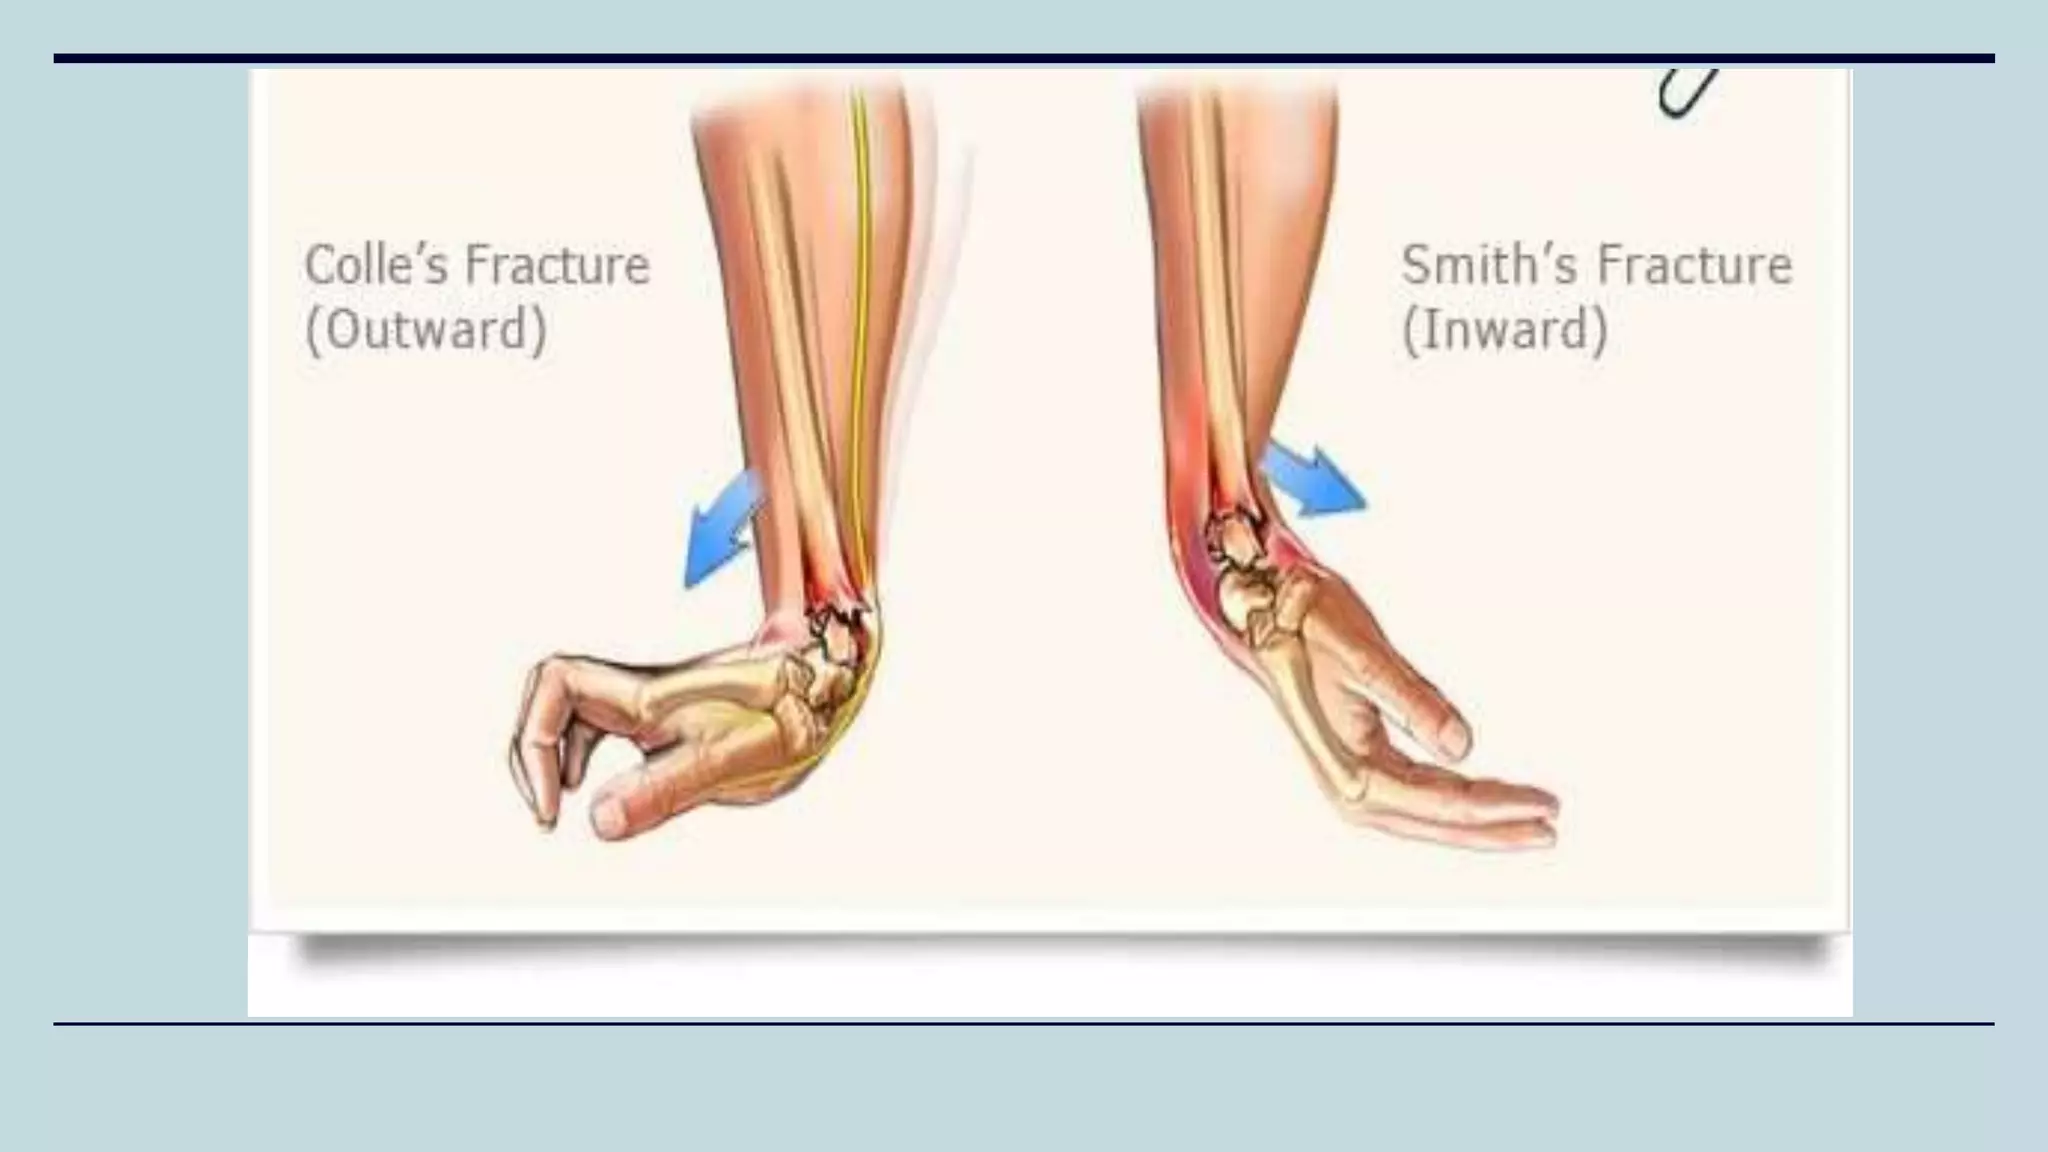

• Most common fracture of the distal radius

(Cortico-cancellous junction)

• Results from a fall on an outstretched hand

(FOOSH)

Colles’ Fracture

• Less common fracture of distal radius

• Unstable fracture

• Fall on the flexed wrist with forearm fixed in supination

• Distal fragment is displaced volarly and proximally (apex

dorsal)

• Direct blow to dorsum of the wrist

• Treatment is generally done by open reduction and

internal fixation due to unstability

Smith’s Fracture